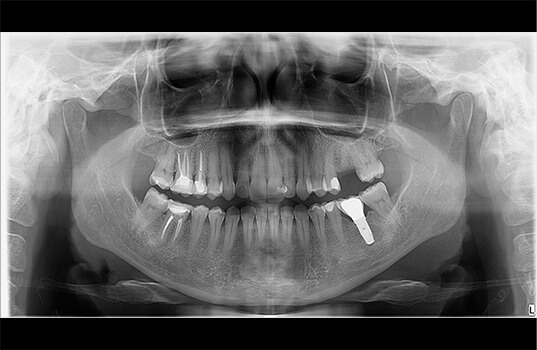

A Radiografia Panorâmica é uma radiografia de boca que fornece uma visão ampla dos dentes, mandíbula e maxila. É usada na odontologia para ajudar a identificar problemas dentários, como cáries, infecções, fraturas e outros problemas ósseos. Além disso, a Radiografia Panorâmica também pode ser usada para planejar tratamentos dentários, como a colocação de próteses e implantes dentários, como também para avaliar o desenvolvimento de tratamentos já realizados.

Na Radiografia Panorâmica, o paciente é posicionado na máquina de Raio-X e precisa ficar parado por alguns segundos enquanto a máquina faz a imagem. A imagem resultante mostra uma visão ampla da boca, mandíbula e maxila, permitindo aos dentistas visualizarem as estruturas ósseas e dentárias de uma só vez.